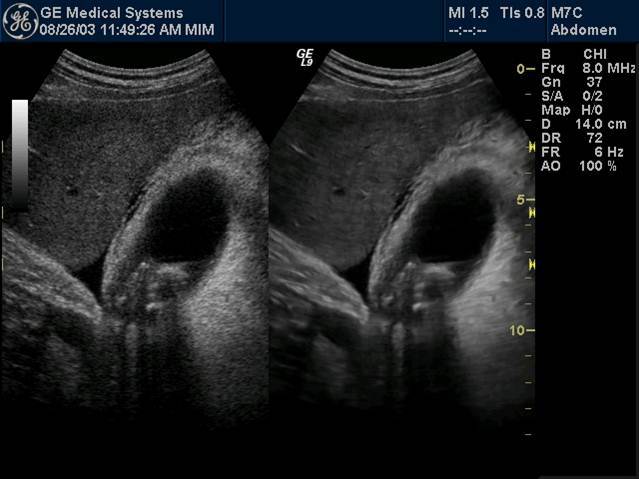

Tumefactive sludge

Sludge